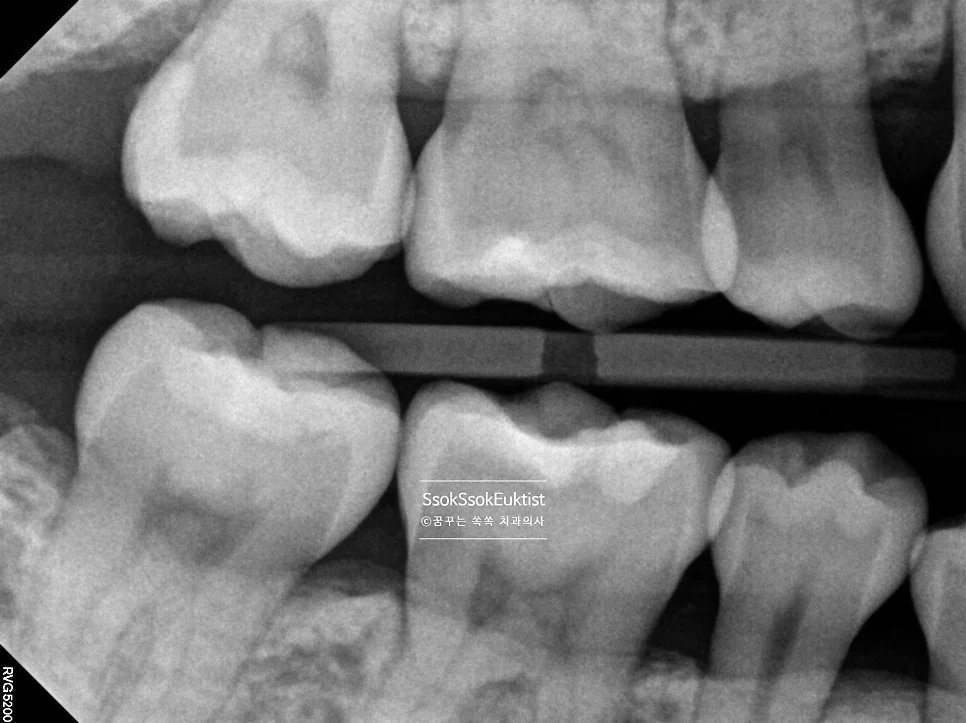

상악 교익 방사선 사진 충치 없음

상악 교익 방사선 — 충치 없음

하악 교익 방사선 사진 충치 없음

하악 교익 방사선 — 충치 없음

치아 사이 충치를 가장 잘 볼 수 있는 교익 방사선(Bitewing X-ray) 사진으로도 치료가 필요한 치아는 찾을 수 없었는데요.

왼쪽 위 앞니의 치경부 우식이 하나 있어 이것을 제외하고는 정말 스케일링만 진행하면 되는 상황입니다.